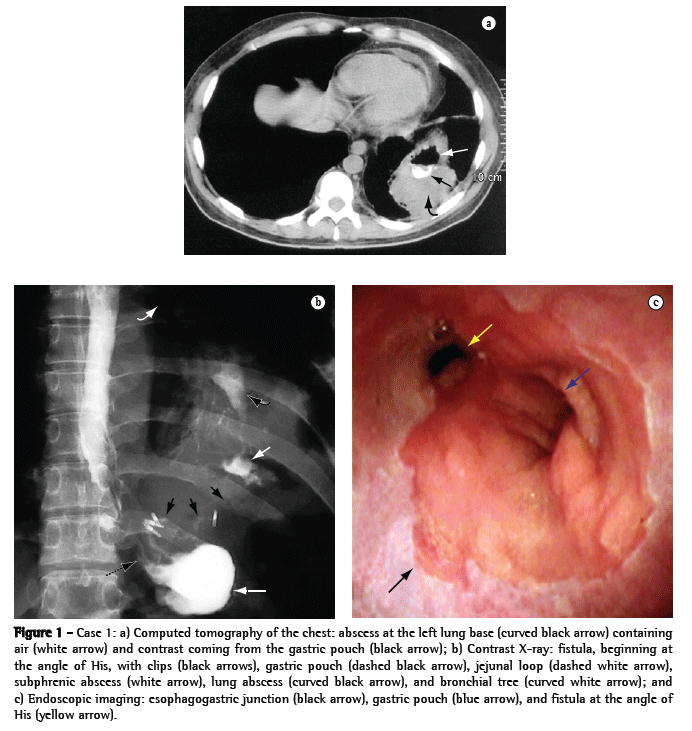

A 44-year-old male patient who underwent Fobi-Capella surgery by laparoscopy in order to control morbid obesity underwent a second operation 48 h later to relieve intestinal obstruction. Two months later, two endoscopic balloon dilatation sessions were carried out in order to correct stenosis of the gastrojejunal anastomosis. Subsequently, the patient presented projectile vomiting, productive cough, fever, and pain in the left thoracoabdominal region upon deep breathing, and a nodule of 7 cm in diameter was detected in the left lung base through computed tomography of the chest (Figure 1a). The patient presented clinical improvement after antibiotic therapy, respiratory therapy, and monitoring in the pulmonology department. However, there were two recurrences within an interval of three months, at which point a gastrobronchial fistula was diagnosed through X-ray (Figure 1b) and endoscopic (Figure 1c) imaging, which revealed an opening of 10 mm in diameter at the angle of His, through which it was possible to pass the endoscope until it reached a small subphrenic cavity where an internal opening of the fistulous pathway toward the bronchial tree could be seen. The attempt at correction via laparoscopy was unsuccessful, and the only procedure carried out was a gastrostomy (for the purpose of nutrition) in the excluded stomach. Using an electric scalpel, we performed endoscopic section of the gastric stenosis and of the septum located between the fistula and the gastric pouch, together with balloon dilatation (20 and 30-mm balloons; Boston Microvasive, Boston, MA, USA), and clips were used in order to close the fistula (Olympus Corp., Tokyo, Japan). Six months later, we observed an increase in the diameter of the gastric pouch, the disappearance of the abovementioned septum, and the definitive closure of the fistula, which resulted in the resolution of the lung abscess.